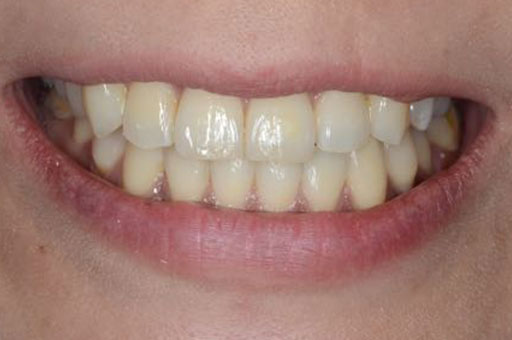

治療後01

治療後02

治療後03

治療期間:3年8ケ月 予後:4年 治療費:¥900,000